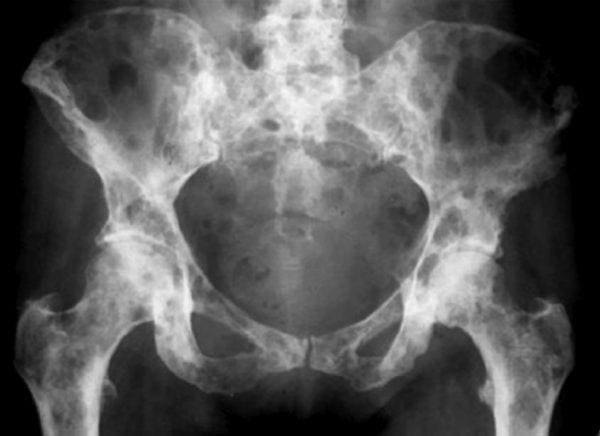

• Pelvis

Breast cancer often behaves in a combined osteolytic and osteoblastic method. Since the cancer cells secrete factors that interact with all the cells in the human skeleton, causing bone destruction, new bone formation, or both, osteolytic and osteoblastic metastatic bone disease happens. Also, breast cancer may commonly cause MBD in the hip and/or pelvis.

• Other imaging tests: The doctor may also order a bone scan. This test can determine if other bones are involved with metastatic bone disease. In select situations, a computerized tomography, or CT, scan and magnetic resonance imaging, or MRI, may be ordered, especially in scenarios where the spine or hip and/or pelvis are involved.

A variety of cancers can commonly cause metastatic bone disease, or MBD, throughout different regions of the human skeleton. Bone metastases can cause painful symptoms, ultimately affecting an individual’s quality of life. Research studies have demonstrated that metastatic bone disease in the hip and/or pelvis is a prevalent health issue associated with breast cancer. Treatment may vary on the progression of the problem.